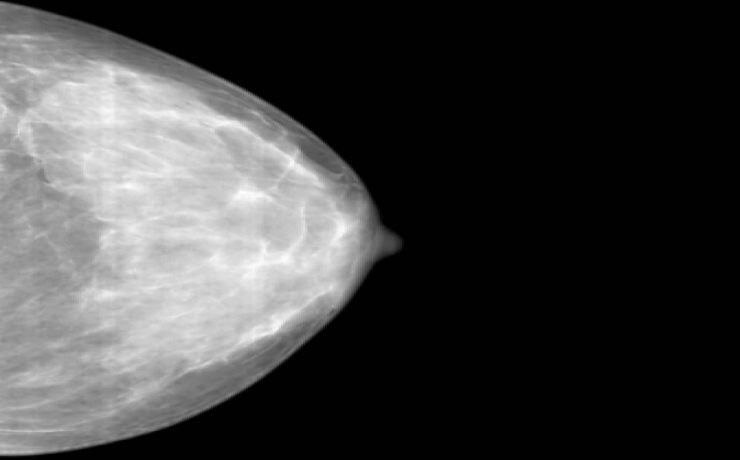

Fibroadenoma de tejido mamario ectópico axilar

Es el tumor benigno más común de la glándula mamaria de mujeres jóvenes. A pesar de que un 95% de las mujeres existe tejido mamario en la axila (cola de mama) y de que incluso en 6 de cada 100 es clínicamente evidente. Los reportes de este tumor en la